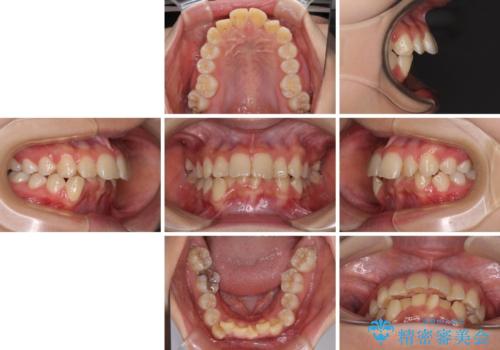

【モニター】出っ歯と八重歯 抜歯矯正でスッキリとした口元に

- 前方に飛び出した前歯と、下顎の八重歯を気にして来院された患者様です。

口元の突出感を改善するため、上下左右の第一小臼歯4本を抜歯し、ワイヤー装置にて矯正治療を行うこととしました。

抜歯矯正により、口元の印象だけでなく、横顔の印象も大きく改善されました。